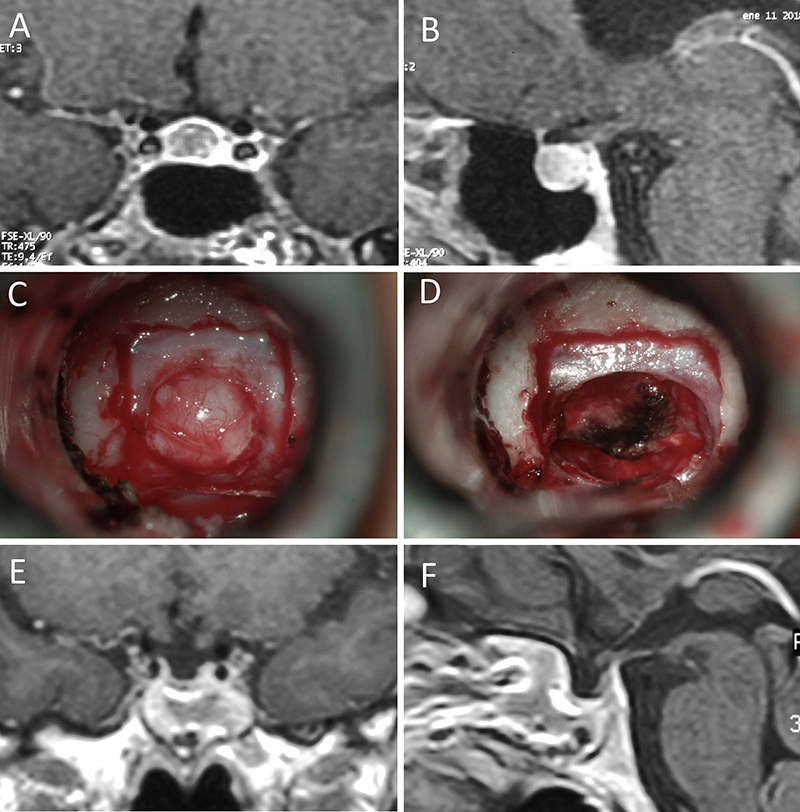

Figura 11: Microadenoma en una mujer de 36 años con Enfermedad de Cushing. Con remisión bioquímica tras la cirugía. A-B: RM preoperatoria; C-D: intraoperatorio; E-F: RM postoperatoria.

Figura 12: Microadenoma en una mujer de 26 años con Enfermedad de Cushing. Con remisión bioquímica tras la cirugía. A-B: RM preoperatoria; C-D: intraoperatorio; E-F: RM postoperatoria.

Figura 13: Macroadenoma en una mujer de 42 años con Enfermedad de Cushing. Con remisión bioquímica tras la cirugía. A-B: RM preoperatoria; C-D: intraoperatorio; E-F: RM postoperatoria.